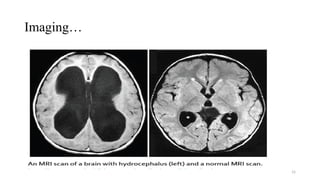

Imaging…

Head CT scan

• Fast, reliable, and does not interfere

with implanted medical devices.

• Usually can be accomplished

without sedation.

• Disadvantages - radiation exposure

MRI

• Modality of choice in patients with

unexplained hydrocephalus

• Superior visualization of

pathological processes in the CSF

pathway, including CSF flow

dynamics.